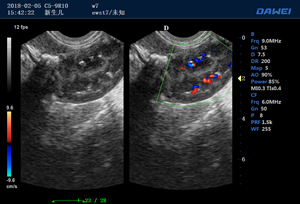

·支持B、C、PW、CW、寬景成像

·實時三維成像(4D)